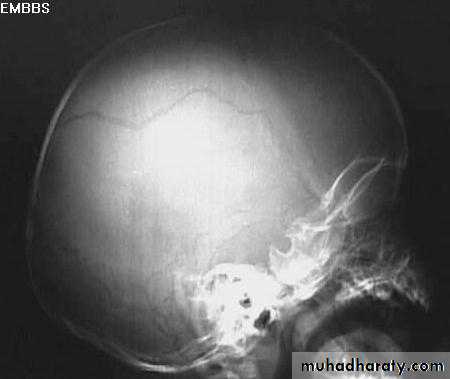

a. Plain skull x-ray

1. Can demonstrate the site and type of a skull fracture.

2. A foreign body can also be seen.

Skull Fracture

nurosurgery